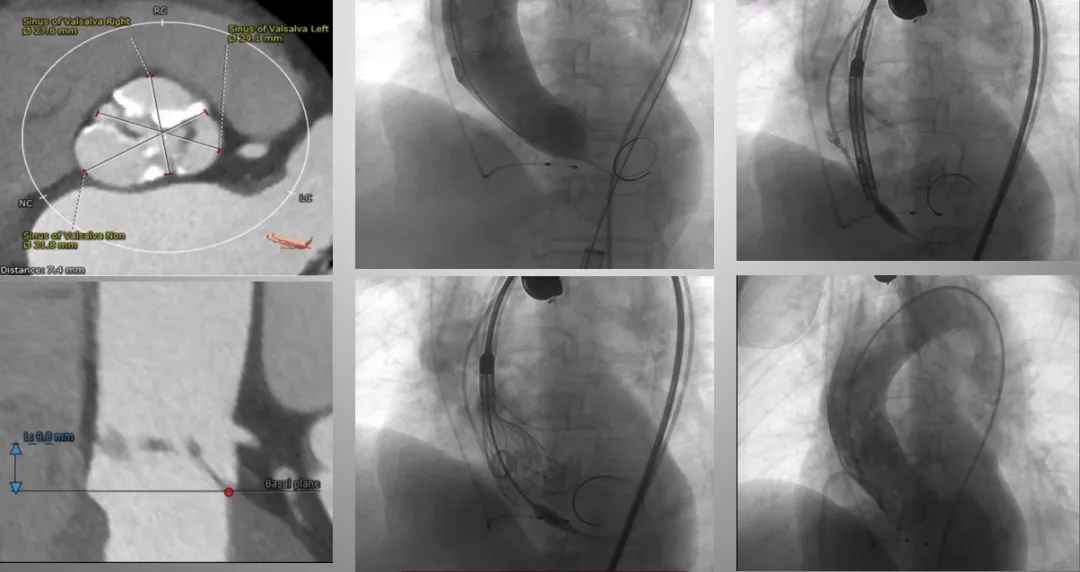

82岁女性,重度主动脉瓣狭窄伴冠心病(一站式)

在临床实践中,冠脉阻塞高风险TAVR的解剖学危险因素主要包括:自体瓣叶过长、存在明显钙化团块或瓣叶过度增厚;主动脉窦部开口高度不足、瓦氏窦尺寸偏小;以及瓣膜植入位置过高等。

(1)预防措施:术前应通过多层螺旋CT进行细致评估,充分预判风险;术中在球囊预扩张或后扩张时,应结合造影动态监测冠脉灌注状态;必要时实施冠脉保护措施或中止手术。